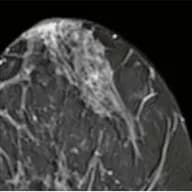

MAMMA MRI

Highest-sensitivity breast imaging, especially for dense tissue.

From CHF 800